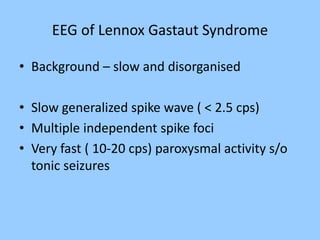

1. The document discusses EEG patterns and findings in various neurological conditions seen in children. It includes descriptions of normal EEG findings as well as abnormal patterns seen in conditions like absence seizures, West syndrome, benign childhood epilepsy with centrotemporal spikes, Lennox-Gastaut syndrome, non-convulsive status epilepticus, subacute sclerosing panencephalitis, and herpes encephalitis.

2. Case studies are presented with clinical histories and EEG findings to illustrate different pathologies. Treatment options are also mentioned for many of the conditions.

3. International standards for EEG electrode placement and recording parameters are reviewed. Characteristics of different EEG waves, amplitudes, and patterns are described.